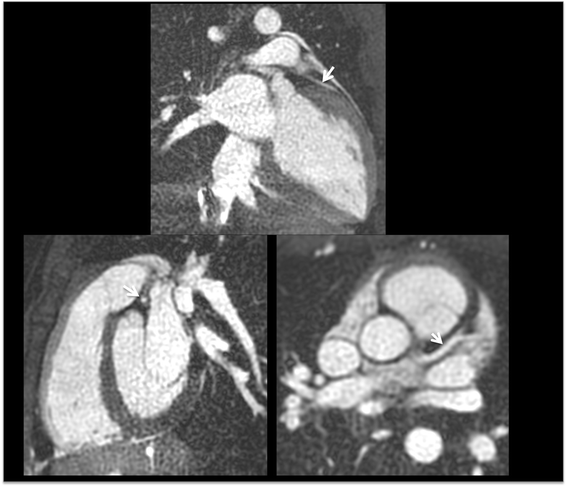

Background: Coronary magnetic resonance angiography (MRA) is usually obtained with a free-breathing navigator-gated 3D acquisition. Our aim was to develop an alternative breath-hold approach that would allow the coronary arteries to be evaluated in a much shorter time and without risk of degradation by respiratory motion artifacts. For this purpose, we implemented a breath-hold, non-contrast-enhanced, quiescent-interval slice-selective (QISS) 2D technique. Sequence performance was compared at 1.5 and 3 Tesla using both radial and Cartesian k-space trajectories.

Methods: The left coronary circulation was imaged in six healthy subjects and two patients with coronary artery disease. Breath-hold QISS was compared with T2-prepared 2D balanced steady-state free-precession (bSSFP) and free-breathing, navigator-gated 3D bSSFP.

Results: Approximately 10 2.1-mm thick slices were acquired in a single ~20-s breath-hold using two-shot QISS. QISS contrast-to-noise ratio (CNR) was 1.5-fold higher at 3 Tesla than at 1.5 Tesla. Cartesian QISS provided the best coronary-to-myocardium CNR, whereas radial QISS provided the sharpest coronary images. QISS image quality exceeded that of free-breathing 3D coronary MRA with few artifacts at either field strength. Compared with T2-prepared 2D bSSFP, multi-slice capability was not restricted by the specific absorption rate at 3 Tesla and pericardial fluid signal was better suppressed. In addition to depicting the coronary arteries, QISS could image intra-cardiac structures, pericardium, and the aortic root in arbitrary slice orientations.

Conclusions: Breath-hold QISS is a simple, versatile, and time-efficient method for coronary MRA that provides excellent image quality at both 1.5 and 3 Tesla. Image quality exceeded that of free-breathing, navigator-gated 3D MRA in a much shorter scan time. QISS also allowed rapid multi-slice bright-blood, diastolic phase imaging of the heart, which may have complementary value to multi-phase cine imaging. We conclude that, with further clinical validation, QISS might provide an efficient alternative to commonly used free-breathing coronary MRA techniques.